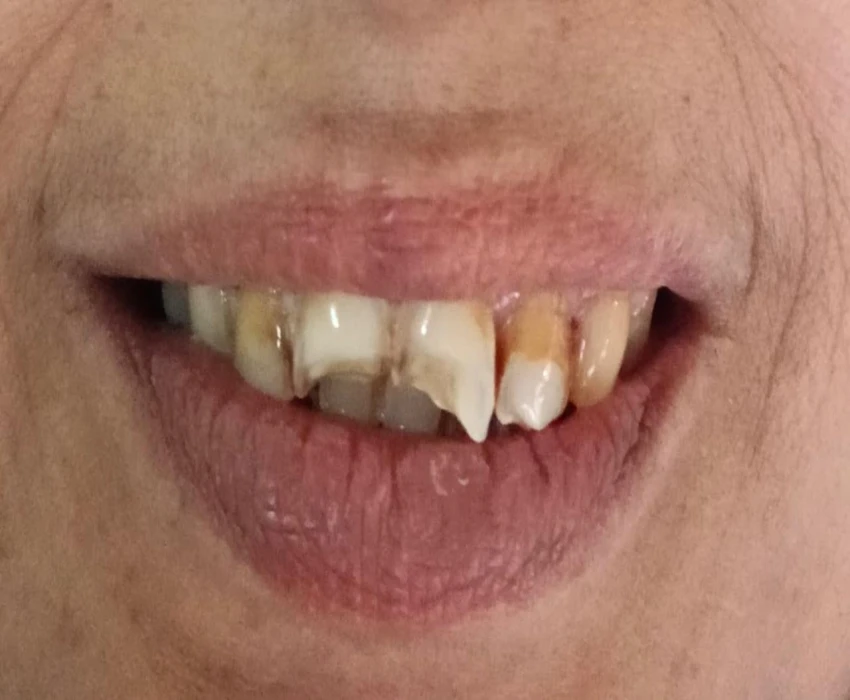

Composite resin restorations have become an integral part of contemporary restorative dentistry and can be called “star of minimal invasion” due to its conservative concepts. The direct composite veneering allows restoring the tooth in a natural way and preservation of sound tooth structure when compared to indirect restorations.